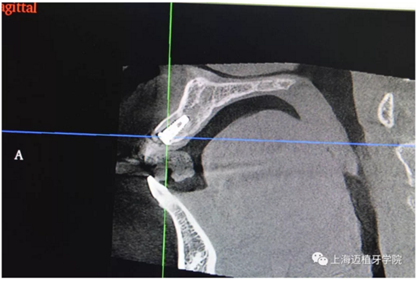

主訴:前門(mén)外傷牙根折要求修復(fù)?現(xiàn)病史:前門(mén)牙外傷,劈裂至根部,無(wú)法固定及其他修復(fù),要求種植?檢查:11牙冠2/3缺損,唇腭向劈裂,唇部紅腫。 CT示根折, 骨寬度9.47mm,距鼻底12.34mm,Ⅲ類骨。 口腔衛(wèi)生一般

放置平行桿

CR片